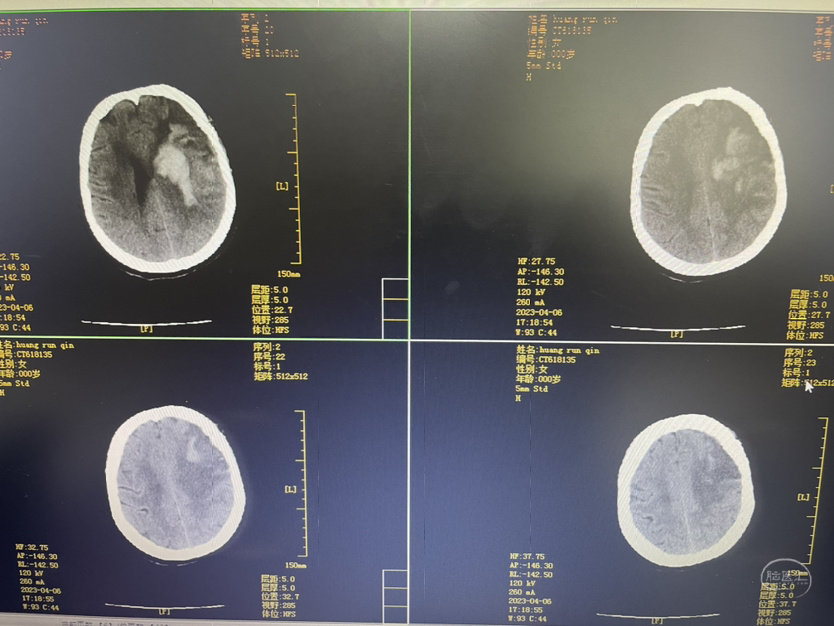

术后第一天

术后第三天

术后第五天

术后第十一天

术后第一个月

夹闭术后两个月,出院后一个月!再次出血,血肿量大,患者清醒!转上级市级医院,拟予介入栓塞后清除血肿